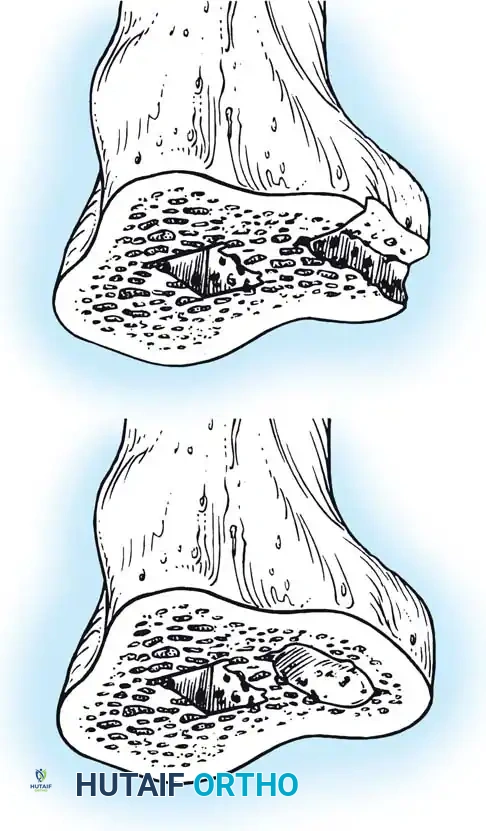

⚠️ Surgical Warning: Patellar Tendon Avulsion

During all maneuvers that place tension on the extensor mechanism—especially knee flexion and patellar retraction—pay careful attention to the patellar tendon attachment at the tibial tubercle. Avulsion of the patellar tendon is a devastating complication that is notoriously difficult to repair.